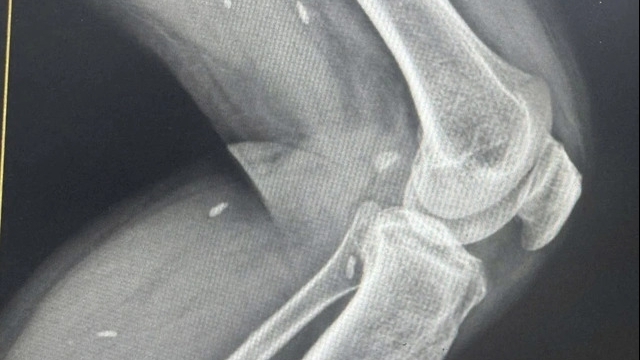

Chỉ trong 6 tháng đầu năm 2025, bệnh viện đã thực hiện 26 kỹ thuật lâm sàng mới, trong đó có những kỹ thuật đòi hỏi trình độ chuyên môn cao như: Phẫu thuật thay toàn bộ khớp gối, phẫu thuật nội soi phụ khoa chuyên sâu, phẫu thuật ung thư vú và tạo hình thẩm mỹ, tán sỏi thận qua da bằng ống mềm, tạo hình thân đốt sống bằng bơm cement sinh học, thay đĩa đệm nhân tạo cột sống thắt lưng – cùng, tiêm thuốc tiêu sợi huyết điều trị đột quỵ não trong giờ vàng…